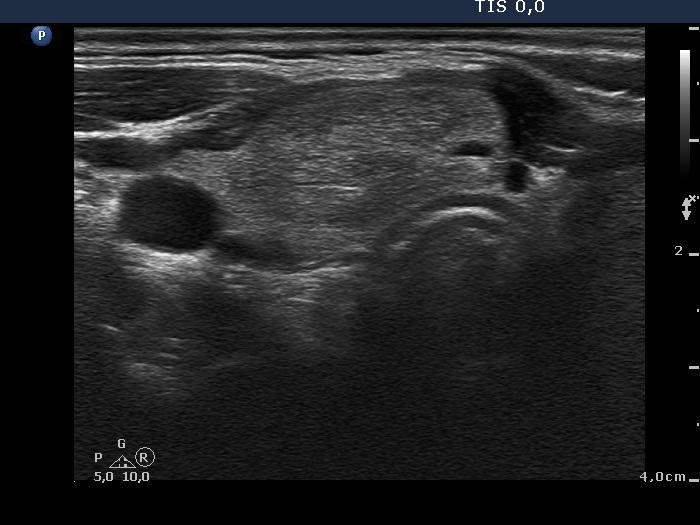

Ethanol sclerotherapy: non-toxic solid nodules - Case 5

Twelve years after the therapy (ultrasonographic picture 1)

Right lobe, horizontal scan. The nodule in the right lobe remained unchanged.